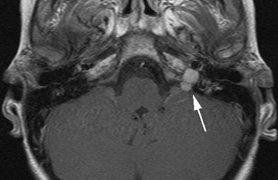

NEUROLOGIC FINDINGS.

- Schwannomas most commonly affect the fifth cranial nerve (CN), but

any cranial nerve may be affected. In contrast to vestibular

schwannomas (CN VIII), these typically do not grow large.84,90 Vestibular schwannomas (acoustic neuromas) are the classic finding

in NF2 (Fig. 7). The risk for malignant transformation is low, but may be higher

with radiation exposure.84,94

- Meningiomas are most likely to affect the spinal cord and supratentorial

part of the cranium.84

- Other tumors: low-grade ependymomas and gliomas may affect the cervical

spine and Brainstem (Fig. 7).84

- Bilateral eighth nerve schwannoma, or

- Positive family history of NF2, plus either unilateral eighth nerve schwannoma or two of the following:

- Neurofibroma

- Meningioma

- Glioma

- Schwannoma affecting other nerve(s)

- Juvenile lens opacity

- Neurofibroma

A significant proportion of cases (20% to 30%) may present with intracranial meningioma, spinal tumors, or cutaneous tumors. Vestibular schwannomas may account for as little as 15% to 30% of presenting signs in children. Thus, expanded criteria have been proposed to include individuals with multiple schwannomas/meningiomas who have not developed vestibular schwannomas as yet and do not have a clear family history.84